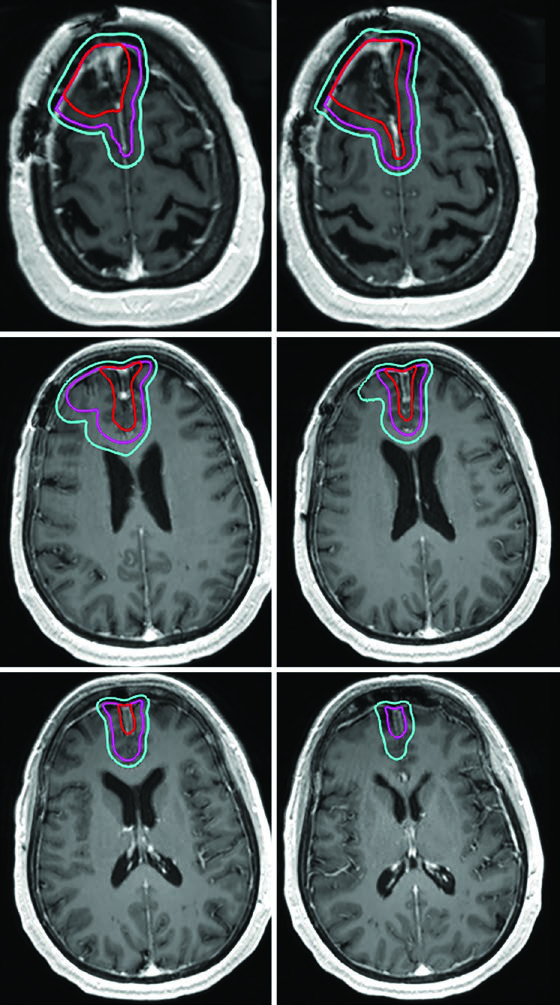

Grade II and III Meningioma and Hemangiopericytoma

Meningiomas are the most common primary intracranial tumors in adults, with fewer than 30% classified as atypical (WHO grade II) or malignant (WHO grade III). For grade II meningiomas, adjuvant radiotherapy can be considered after gross-total resection and is recommended after subtotal resection. For grade III, adjuvant radiation is recommended regardless of resection extent. Adjuvant radiation is also recommended for all hemangiopericytoma resections. For benign CNS tumor management, see our dedicated article on benign CNS tumors.

A critical distinction for grade II/III meningiomas: since these tumors can invade bone and brain parenchyma, the skull and normal brain are not necessarily natural barriers to tumor spread. If operative or pathology findings demonstrate brain invasion, CTV margins must include brain parenchyma at risk. For recurrent grade II lesions, evaluation of the original dural attachment site at initial diagnosis is also recommended.

| Grade II meningioma (upfront) | 54–59.4 Gy (1.8 Gy/fx) | Post-op cavity, residual tumor including suspicious dural/bone involvement on post-contrast T1 | 0.5 cm anatomically constrained | 0.3–0.5 cm |

| Grade II meningioma (recurrent) | 54–59.4 Gy (1.8 Gy/fx) | Same + evaluation of prior dural attachment at initial diagnosis | 0.5–1.0 cm constrained | 0.3–0.5 cm |

| Grade III meningioma (upfront or recurrent) | 59.4–60 Gy (1.8–2 Gy/fx) | Same + prior dural attachment evaluation | 1.0–1.5 cm constrained | 0.3–0.5 cm |

Hemangiopericytoma deserves special mention. While the 1.5 cm CTV expansion follows the standard pattern, unlike meningiomas, the entirety of involved bone must be included without reduction — the infiltrative nature of these tumors warrants more aggressive coverage.